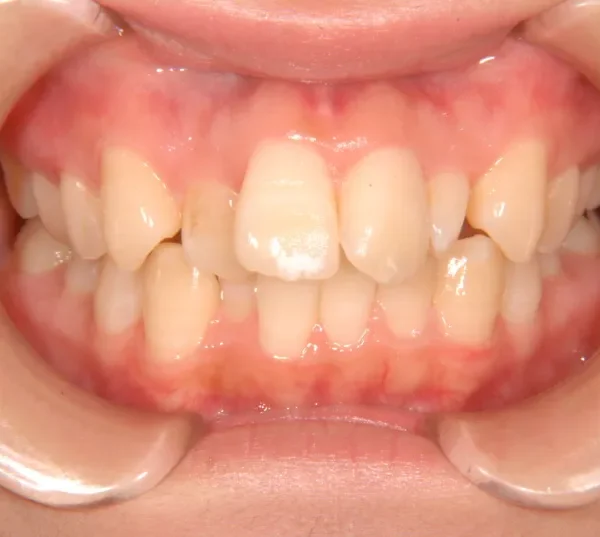

初診時年齢 19~29歳 (女性) 主訴 ガタガタ・90度ねじれている

診断名 叢生・上顎前突 装置名

奥歯が内側と前方にかたむき上下の歯がガタガタに生えています。

90度ねじれた歯もあります。前歯も出っ歯になっています。

歯は抜かず、歯科矯正用アンカースクリューを用いて治療しました。